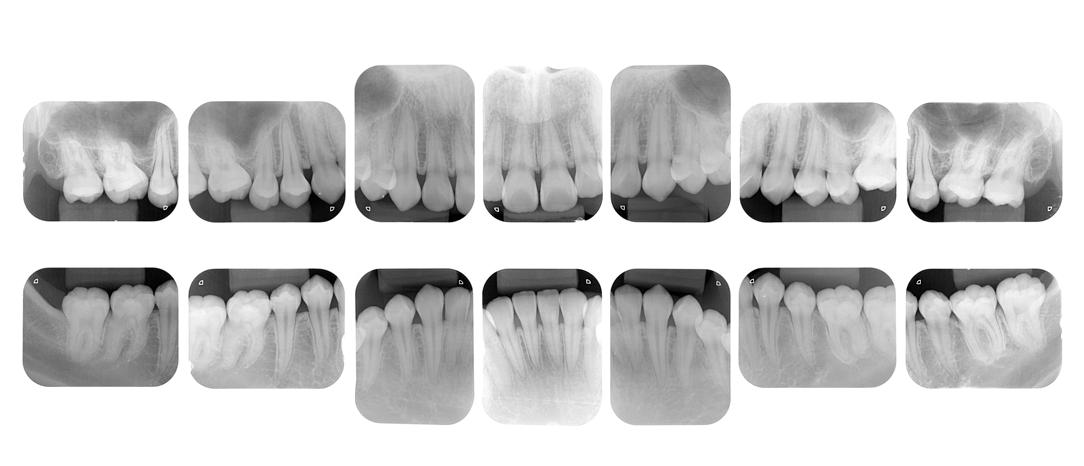

精密検査と診断

まず、現在のお口の状態を詳しく把握するため、レントゲン撮影や歯周ポケットの深さの測定、口腔内写真撮影などを行います。これらの検査結果に基づき、歯周病の進行度や原因を正確に診断し、患者さん一人ひとりに最適な治療計画を立案します。

レントゲン撮影口腔内写真撮影